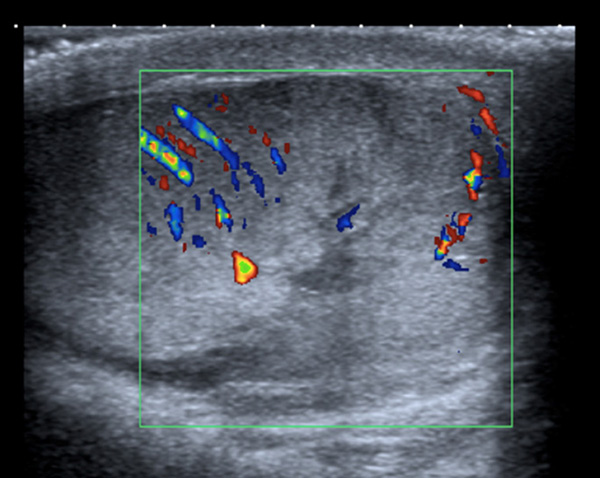

Fig. 1. Ecografía testicular, donde se objetiva aumento de tamaño escrotal derecho con engrosamiento de cubiertas y con alteración del contorno del testículo, en su polo inferior, compatible con rotura de la túnica albugínea. El testículo derecho conserva flujo Doppler color y pulsado en su interior en todo su parénquima.